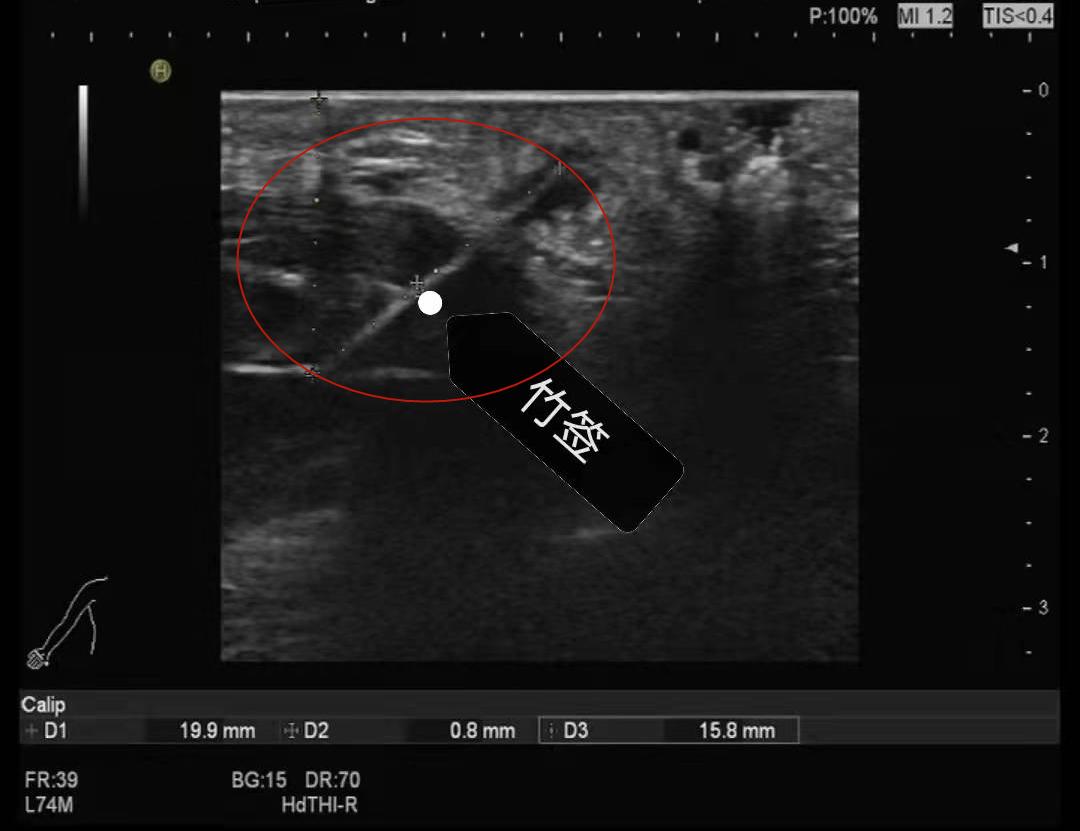

超声诊断科医师将探头放置在李先生红肿的右手掌上时,发现他的手掌皮下软组织内直达大鱼际肌里有一根长达25毫米的细长异物斜行其中,异物的最外端距离手掌皮肤深达8毫米,还有小片的炎性渗出区,很有可能形成了脓肿。

“我当时明明把刺给挤出来了呀!”李先生有些不敢置信,直到他顺着医师的指示,看到超声显示器上那根又长又直的条形物。

之后,在医院骨外科通过手术,深入李先生手掌的那根长达25毫米的竹刺被完整地取出。手掌内部、竹刺的外端处果然如B超所见,已长出了一个小脓肿。经过局部清创消毒,一周后,李先生的手掌终于恢复如初。

超声诊断科主任李涛介绍,竹签、木屑等物在超声下显示为强回声,与周边组织有明显的声阻抗差异,通过超声检查不仅可以明确位置和大小,还能显示其内部结构和前后边缘的界面。超声检查无辐射且可重复性好,安全性高又经济,是排查浅表组织内异物的首选检查方法。